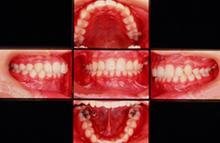

・CASE 2 ~ 八重歯 ~

治療前 12歳5ヶ月

治療後 13歳11ヶ月

治療後 10年後 24歳2ヶ月

CASE 2 ~八重歯~ 上下の歯が凸凹してよく噛めない。

治療前(初診時年齢)12歳5ヶ月の女児

歯が磨きにくい

マルチブラケット装置(表側ワイヤー装着)上下左右第一小臼歯を抜歯して治療しました

治療後 13歳11ヶ月 治療期間1年6ヶ月 治療費700,000円

副作用とリスク(歯の痛み、歯が磨きにくい、口内炎、しゃべりづらい、歯根吸収、歯肉退縮、後戻り、治療期間ついて説明しました。)

保定終了後 7年6ヶ月 24歳2ヶ月